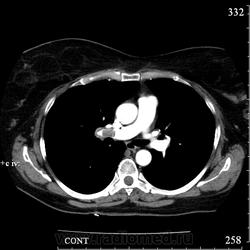

Коллега Mitkamfer спрашивал: "Может из наших коллег еще кто свои наблюдения покажет". Представляю случай ТЭЛА у женщины 57 лет с тромбозом подвздошной вены и распространением тромба в нижнюю полую вену.

Клиники особой не было, исследование делали с целью, а нет ли у нее еще и ТЭЛА. При КТ-ангиографии признаки пристеночных тромбов в правой и левой легочной артериях и единичных мелких пристеночных тромбов в мелких ветвях нижнедолевых артерий с обеих сторон, организовавшихся (лентовидных) тромбов в левой легочной артерии. При этом диаметры легочного ствола, правой и левой ЛА не расширены. Как видите, они такие разные, эти ТЭЛА

Изменения в легких при этом весьма скромные: в правом легком особых изменений нет, в левом - признаки организовавшегося инфаркта легкого - радиальные фиброзные тяжи в базально-латеральном сегменте нижней доли левого легкого.

Рисунок 32. Дополнительные КТ-ангиографические признаки ТЭЛА у больной 58 лет.